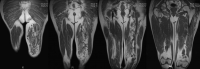

Aneurysmal bone cyst metatarsal. Benign looking expansion of the distal end of the second metatarsal. The lesion is cystic with fluid-fluid levels evident on the STIR image.

16-year-old girl complaing of pain and swelling of the foot.